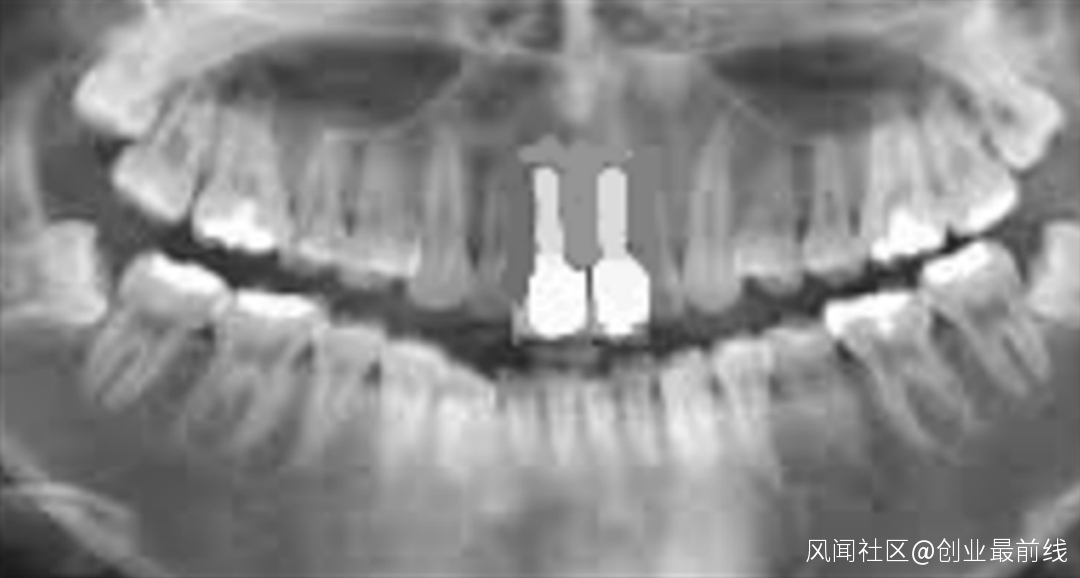

(圖 / 患者植入植體 本圖版權為禎諾ZENOIS,由好牙醫提供)

(圖 / 患者種牙效果 本圖版權為禎諾ZENOIS,由好牙醫提供)